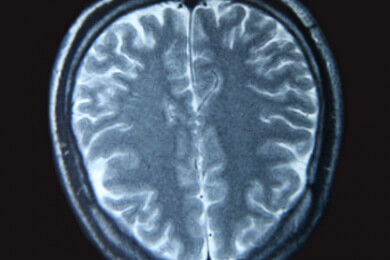

Im Schlaf entspannen die Muskeln, auch die Muskeln des weichen Gaumens, zwischen Zungenansatz und Gaumenzäpfchen. Die Folge: Die Luftwege werden verschlossen und im schlimmsten Fall kommt es zum Atemstillstand.